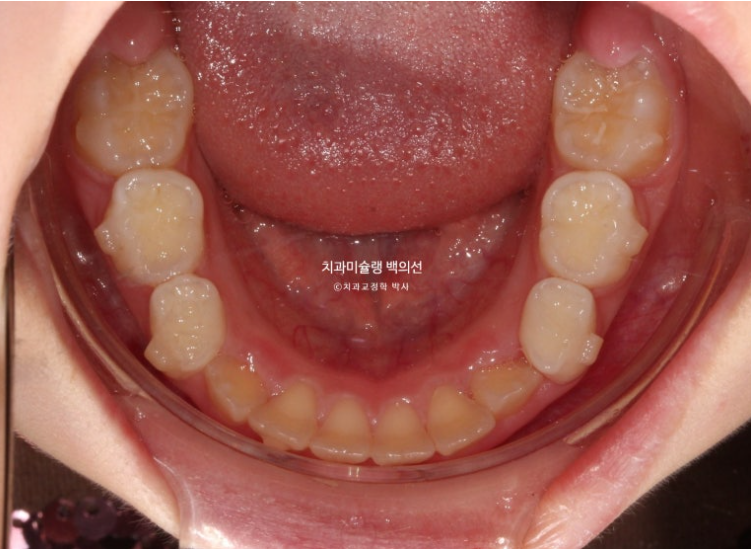

아랫니도 공간이 많이 부족합니다.

골격분석상 하악골 여성장을 동반한 무턱으로 진단되어 치료 목표는

-

악궁확장을 통한 덧니 해소

MA 기능으로 하악성장 유도

이 두가지가 되겠습니다.

손 엑스레이 성장판 분석한 결과 최대 성장기가 시작되는 시점이라 타이밍도 아주 좋습니다.

인비절라인 퍼스트로 권유드렸고 치료를 시작했습니다.